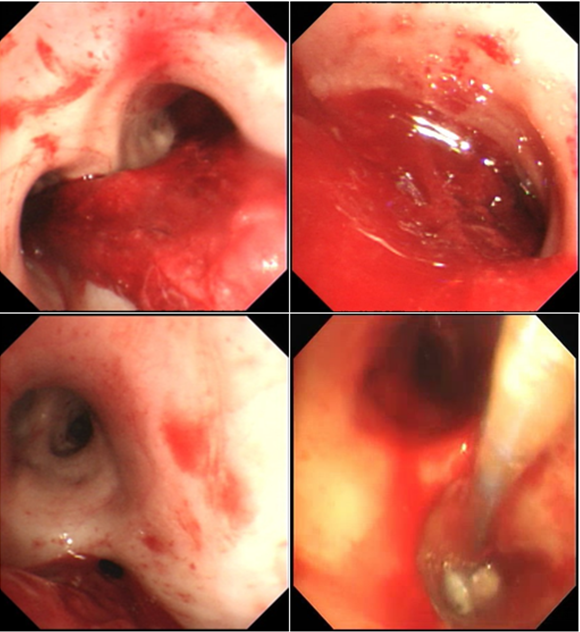

气管镜下可见患者右中间段支气管已被血凝块完全阻塞,右上叶后段和前段大部分也被血凝块阻塞(图3)

图片

图3  气管镜下所见

这种情况下,我们首先在硬质支气管镜下用纱布快速填塞右中间段的支气管。填塞后使用可弯曲支气管镜冷冻探头清理右上叶后段和前段的血凝块。当尝试清理右中间段支气管血凝块时,发现气道内还有少量渗血,因此再次使用明胶海绵进行填充,观察没有活动性出血后插入双腔气管支气管插管,支气管镜下确定位置无误,然后转运到导管室进行支气管动脉造影。